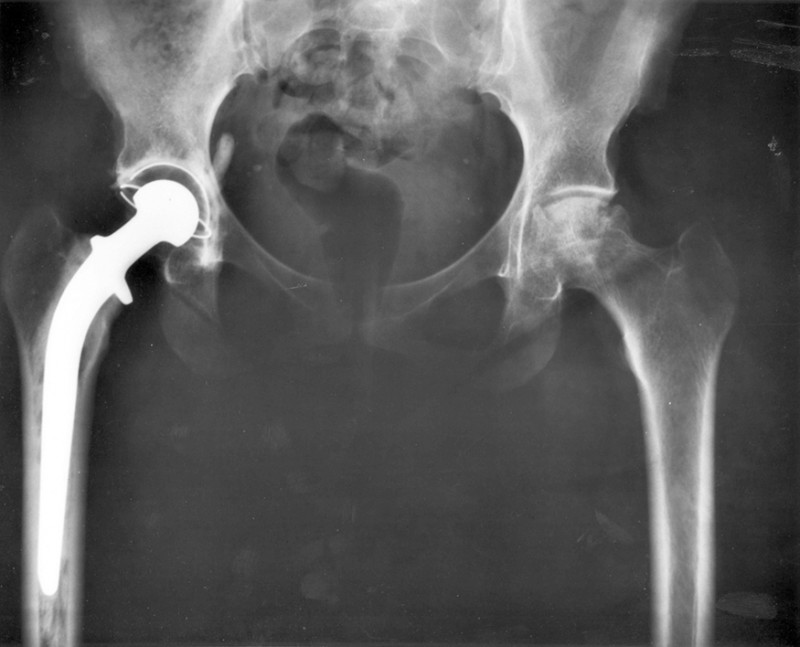

An x-ray image of a person’s hips. The right hip joint (on the left in the photograph) has been replaced. A metal prosthesis is cemented in the top of the right femur and the head of the femur has been replaced by the rounded head of the prosthesis. A white plastic cup is cemented into the acetabulum to complete the two surfaces of the artificial ball and socket joint.

Total hip replacement surgery has become a common procedure. The head (or ball) of the patient's femur fits into a cup that has a hard plastic-like inner lining. (credit: National Institutes of Health, via Wikimedia Commons)

Describe the forces on the hip joint. What means are taken to ensure that this will be a good movable joint? From the photograph (for an adult) in the figure above, estimate the dimensions of the artificial device.